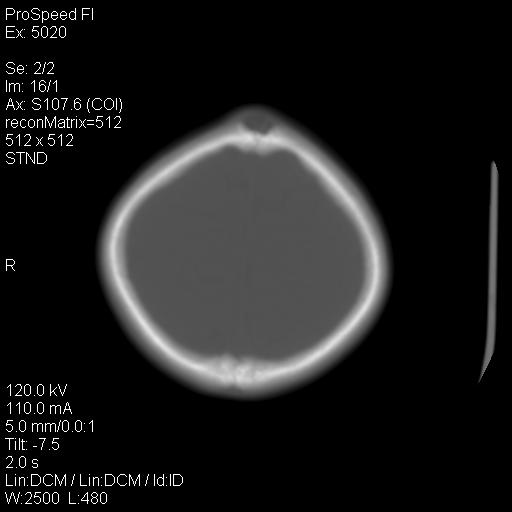

标题: PED1637:M 6Y 顶部无痛性包块两月。 [打印本页]

标题: PED1637:M 6Y 顶部无痛性包块两月。

2、颅骨局部缺失,边缘光滑、整齐

颅骨的病损表现为内外颅骨板层不规则的锋利的破坏,形成“斜边缘”,有一定的特点

颅骨为好发部位,生长缓慢,常位于顶骨、枕骨及颞骨,表现为颅骨缺损,呈圆形或椭圆形,边界清,无硬化